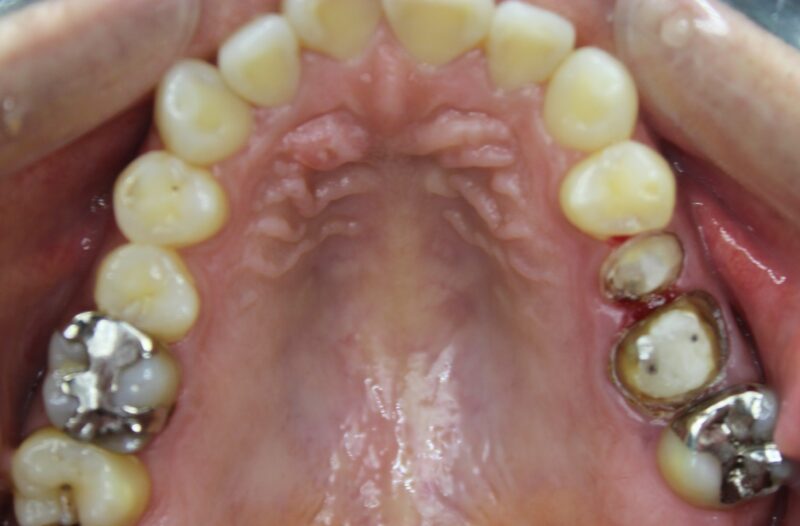

下の写真はメタルコアを外した後です。

歯の中が黒く酸化しているのがわかります。